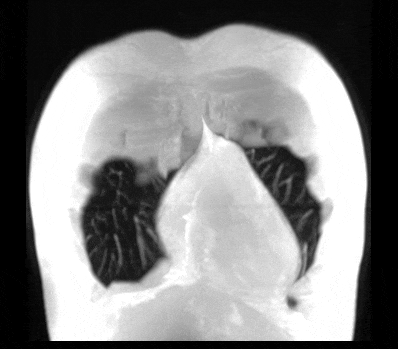

“静音”血管成像

高分辨血管壁成像

UTE 肺部成像